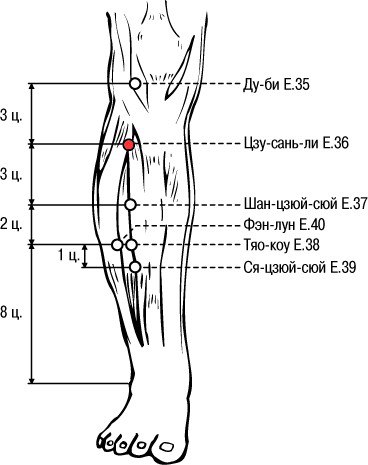

Селение в трех цунях от колена…

Эта точка - Цзу-сан-ли! С китайского «Цзу» переводится, как

нога, «сань» — значит три, «ли» — селение, расположенное на проезжих

путях. Так как китайская медицина включает знания об энергетических

меридианах, то эти каналы и можно сравнить с дорогами, точки — с

селениями, расположенными вдоль дорог. Поэтому точка Цзу-сань-ли - это

селение, расположенное на ноге на три цуня ниже колена.

Чтобы определить точку Цзу-сан-ли, необходимо положить ладонь на колено

так, чтобы пальцы были прижаты к голени, тогда кончик безымянного

пальца укажет на «точку ста болезней». Она расположена книзу от наружных

краев коленных чашечек, в стороне от бугорков на больших берцовых

костях, в небольших углублениях.